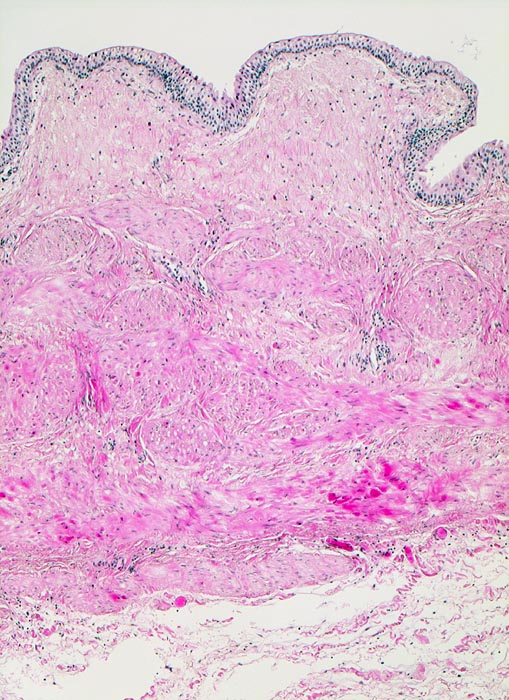

PathoPic ID 4198 - normaler Ureter

normaler Ureter

Normalbefund

Ureter

Niere, Harnwege

Mehrreihiges Urothel ohne Atypien. Darunter die bindegewebige Submucosa und die aus mehreren Lagen bestehtende glatte Muskulatur der Ureterwand.

Histologie

50